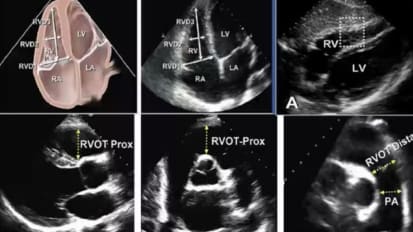

Chapters Transcript Video A Programmatic Approach to Lipid Management in 2023 Dr. Talreja details the epidemiology and pathophysiology of dyslipidemia. I'm honored to be able to talk to you about this topic. A programmatic approach to lipid management in 2023. And I know it's only 2022, but like a good chess match that has a beginning, middle and end game. I've crafted these slides to sort of tell the story of where we are and where we're heading before I do that. I wanna give a quick moment of recognition to the trainees who gave talks at this year's Heart of Innovation program. They were recognized during the program, but our time schedules were a bit messed up. There were a tremendous series of talks from a number of our trainees. They did a fantastic job and I can't wait to see what next year is gonna bring, calling out our 1st, 2nd and tie for third place winners who are getting cash awards. And uh, and the joy of recognition for success, um, kudos to all those and those of you listening as trainees, pay attention to next year's Heart of Innovation Conference. Another chance again, amy will get together with all you guys afterwards with your certificate book and uh, and the award. So part of Innovation again this coming year, I'll launch right into my topic. And I'm gonna tell you, I'm gonna talk really fast. I have a whole lot of slides and I kept trying to condense them and then add more and condense them. This really should be two grand rounds. But since we're ending the year with this one, I only have space for one. These are my disclosures, they're available on the websites as well. So I started with an interest in lipid ology probably a little over a decade ago, one of my partners in cardiovascular associate steve jones lured me into boarding and lipid ology and as I think of the sort of tale of two cities approach to the world. These are the two differences I see in my clinic I get referrals of patients with severe aortic stenosis for trans catheter based aortic valve replacement. Those patients typically have a lot of information at their fingertips and they come in knowing exactly what they want. They've read everything and they know where they want to go. In fact were often the ones sort of slowing them down and saying, well we have to think about surgical options. You may not actually need a valve replacement at this point. So, good job learning. But maybe we're not there yet. The opposite is the lipid clinic where the typical consult is a patient who has read this among many books and is skeptical of what is again, clearly lifesaving technology. That has a tremendous value proposition. And it's a real tragedy because as a result it limits what we achieve in prevention, which really is the key at the end of the day. So today we're gonna talk about some epidemiology and path of physiology of dis lipid e mia. We'll talk about lifestyle options and specifically the tremendous opportunities that exist in our community for really changing the course of a disease trajectory for atherosclerotic cardiovascular disease. We'll talk about pharma co therapy options and I'm gonna blitz through quick look at data and what's available and what's new integrated throughout this and especially at the end will be guidelines. And then we'll talk about the lipid program where it is and where it's going. So atherosclerotic cardiovascular disease in 2020 is estimated to affect 30 million Americans 19 million. So two thirds roughly are on statin therapy for some form of this disease entity. 15 million receiving statin therapy were not at the A. C. C. H. A. Recommended goal of an L. D. L. Less than 70. So shocking in this era that we really have so much. We're not even at the halfway point in terms of achieving what we set out as our goals. Obviously atherosclerotic cardiovascular disease is a heterogeneous group of diseases. Those of us in cardiology so often think of coronary disease dancing ACUTE. M. I. Semis and so forth. But stroke P. I. A. And P. A. D. Including aortic disease are really a part of this uh different spectrum of disease. Over the last three decades we've seen a tremendous improvement in cardiovascular mortality. Unfortunately over the last most recent decade of those 3 to 4 decades we actually seeing now an increase in deaths attributable to cardiovascular disease independent of definition. Some of this is perhaps catch up you know no one's immortal and so as we make people live a decade longer eventually we're going to run the course on that time. But some of this is a more complex disease process and there's a lot of other factors this slide calls out in diabetics in particular. We've made tremendous inroads with new therapies and the last time I gave a grand rounds on this topic, Elias carriage from the VMS endocrinology department joined me and he talked about management of diabetics after I talked about methodology. Um what we see again and again is even with the newest therapies, you know think of S. G. L. T. Two inhibitors GLP one ras and other therapies. We have insulin pumps. A diabetic patient still has a 1.5 fold increase in the risk of cardiovascular death compared to the general population leaving that as a particularly vulnerable population. The reason is, and we know the molecular level of what's going on in quite some detail. Amazingly enough, I will say of all the boards I've taken the lipid boards were the most nitpicky and hardest to understand. And part of it is the path of physiology we're talking about here is so complicated that even when you sit down and try to draw out everything we know there are huge gaps in the mechanisms that work. But what we do know is a probie bearing lipoproteins. Think of LDL and particles like that are really where the action's at in terms of creating inflammation in the vessel starting the process of plaque accumulation and going on to create ultimate calcification. We know a lot about lipid metabolism. The average american consumes 200 to 400 mg of cholesterol a day. The average american produces between 612 100 mg of cholesterol a day. So bad diet plus good genes or good diet plus bad genes leave us with some variability in how patients respond. We know HDL can be beneficial. We know LDL and the particles like it can ultimately lead to plaque accumulation. And ultimately, If you want to think of this in a fairly simplistic fashion, it's LDL level, circulating LDL times the number of years of exposure to it. That equals your total plaque burden and causes atherosclerotic cardiovascular disease. We can't affect time directly, but we can get patients on good therapy and give them a long run on that good therapy to try to prevent accumulation of plaque and that's really the goal of everything we're talking about in the next 40 minutes. So first and foremost, let's talk about lifestyle modification. This is clearly underutilized, although we've made a lot of inroads in this, calling out the 2022 American Heart Association statement on the comprehensive management of cardiovascular risk factors for adults with type two diabetes. We see that lifestyle modifications are the first thing we think about quitting smoking, exercising, eating right, losing weight. Then we think about social determinants of health. We think of cardiovascular imaging, I think in this era we still massively underutilized, fairly inexpensive tests. Think of coronary calcium scores. Think of cT imaging. We have great stress testing and for those patients that needed cardiac catheterization. But compared to a decade ago, there's there's obviously a lot of ways to pick this process up early in the game. And then we have a great number of medications, especially in the general population and in diabetics that can impact this disease process quitting smoking. I'm just gonna show this slide enough said critical, critical um dietary patterns. This is from an A. H a publication plant based diet will call out specifically as what recognizes one of the healthiest diets out there now. Of course no diet is effective if a patient is not going to follow it. So there are other opportunities available for us. And we've done study work on some of these, I will say, unfortunately, the worst diet out there fits with our geographic location. The southern diet is really the one that is known to increase the risk of cardiovascular disease and heart failure. Physical activity. Any level helps increasing mets, especially up to uh the relatively moderate level has a dramatic impact on all cause mortality. And that's why cardiac rehab programs are so useful. It's tough practicing cardiology in your local community for those of us that want to go out and grab some fast food, you have to hide if you're a cardiologist, I don't get there much. But among the billions and billions served. I try to be not in that pool too much and most of our patients need to do the same. So years ago, almost a decade ago we did a study. Many of the folks in this room were part of this are supported one way or another an investigation of four commonly used diet, plant based mediterranean, paleolithic and dash diets. I showed this in a forum here, but it's been about a decade. This is collaboration between our area and the University of Virginia. We offered 100 patients that self selected their their arm. Four commonly recommended diets and what we saw was interesting just quickly calling out everyone lost weight or every group lost weight anywhere from 4 to 5 up to £12 over a period of 60 days. B. M. I improved blood pressure improved pretty remarkably. This is what you would expect from one or two medications. An average blood pressure drops systolic a between 10 and 15 mm of mercury. For patients that complied and calling out some lipid changes. We saw pretty impressive reductions in everything from triglycerides to LDL, including highly specific markers like L. D. L. P. You see in this, the vegan group really had the most remarkable decrease in LDL. P. 100 and 40 point decline. Diet is extremely effective. Now this was a decade ago. What about since then I'm gonna come back to our rehab programs. I've worked with them to get some of the data from our patients locally over the last quarter for those patients who can't get where they need to be or starting too late in the game for diet to be sufficient pharma co therapy becomes important. There are a lot of trials in this spectrum. These are great trials. We participated in a lot of them and we'll talk about some of the key ones as we look at what's going on. So if we think about lipid lowering agents, our mechanistic understanding of what's going on has allowed the development and testing of specific agents and this is from the journal American College of Cardiology. There are five specific mechanisms called out here. Number two is our H M G. Co a reductase inhibitors statins, very effective, very underutilized patients are very well aware of the potential side effect mechanism. And importantly, even with statins which are the 1st, 2nd and 3rd line therapy, a lot of patients we looked at the numbers earlier cannot get to their target therapy, whether it's related to compliance or insufficient potency. One above the status in the same pathway of production of cholesterol within the parasite is a teepee citrate lies we have a blocker for that which works upstream of statins and can be used with them. That's empathetic acid. Number three. The NPC one. L one receptor is where um I've works and we'll look at that Number four is through interactions with the pcs K nine protein. And that's where we have new injectable agents that can act directly on that. And then today we'll talk about one of the newest editions which actually works on blocking the transcription of M. RNA for pcs canine production and we'll call all those out and the mechanisms to come. So first we always have to think first and foremost in pharma co therapy about statins. There is absolutely no uncertainty whatsoever about the effectiveness of statins in reducing cardiovascular disease. This is the largest meta analysis of almost 100,000 patients showing reduction in every important endpoint all cause mortality, coronary mortality, M. I. C. H. D. Death stroke and major vascular events. Of course there are some patients that have difficulty tolerating these agents but there's absolutely no question that the value proposition, generic, inexpensive costs with tremendous benefit is there. And so it's incumbent on us to try multiple statins at the highest doses patients, patients can ultimately tolerate in all patients. And again, if you look at these trajectory curves, you've all seen many times before whether we're talking about the secondary prevention curve on the top which has a steeper benefit curve or the primary prevention group which has a slightly shallower benefit curve. There is zero questions across all populations as we lower LDL with statins and actually many non statin therapies follow the same curve. But in this slide we call out, lower is better with statins and we really have to be aggressive about it enough. Said I know this is obvious everyone knows it but it's important to call out again. Where that leaves us though is if you look at the major trials of status in every single trial concorde only statins lower event rate, but there's a pretty high residual event rate in each of the trials as well. You see statistically significant benefits. But we see a 25 to 40% residual risk for recurrent events across every trial. Every population we've looked at and that's the group. We have to do more for so many years ago we were in the improvement study that tested the addition of a on top of statin. There's a lot of things you can criticize. But ultimately what that trial showed us is effectiveness of um I've it took about seven years for the curves to reach statistical significance. It takes a while. But the group on combined as a team I've and statin does better with the number needed to treat a 50 that's statistically significant. And that's why again, is another generically available agent. There is a clear utility for this and we'll look at where it falls in the guidelines more recently, the introduction of psychedelic acid has given us another mechanism to affect lipid production within the liver. Some potential benefits of this are it works in a different area than H. M G co a reductase inhibitors, although it's in the same basic pathway, it is a pro drug that has to be converted to its active element. And interestingly in skeletal muscle there's no conversion enzyme. So in theory potentially less skeletal muscle concern with the OIC acid than we see with statins. So gives us one other option and studies have shown us. While outcome studies are still pending, we have clear data that shows about 15-20% reduction in the largest trials trials compared to placebo for the addition of the OIC acid to a satin. And when we look at the combination of a demise and um and and and talk acid together which is one combination pill, we can get up to a 40% additional reduction. So another therapy, again, no hard points yet, those trials are ongoing but this can be effective in patients either statin intolerant or can't get to their max benefit. Everyone here knows about PCSK nine inhibitors. Again, really, a remarkable example of the benefits of understanding molecular level pathways from initial identification of the relevant genetics and populations out there to FDA approval and outcome studies, we're looking at a period of under 15 years to get this therapy available to us. The idea is P C S K nine is an enzyme our body produces on the left. It's the things that looks like cheetos and orange color and what they do is when they couple together with an LDL particle and an LDL receptor, the PCSK nine results in degradation of that LDL receptor, you destroy your own LDL receptors. They finessed over time. Each LDL receptor recycles about 100 and 50 to 200 times. And this is the natural sin essence mechanism. There are people who genetically don't make pcs K nine and they have a lot of extra LDL receptors because they stay in circulation and they work longer. They tend to have low LDL. And so we've replicated this with available mechanisms based on current molecular biology. Um this is lucca mob one of the available ones monthly or every two week injectable agents available multiple trials in the Oslo program that show us very effective reduction in LDL cholesterol. The LDL has dropped by about 50 to 60% across studies and it's a durable effect with potentially a monthly injection for this. Initial costs were high. Those costs have come down as coverage has improved. And now, in addition to proving that we can get a much larger number of patients to their LDL goals, we see outcomes. This is the LDL cholesterol goals. If you look at the LDL goal on the left of an LDL less than 100 we see that in the standard care therapy which includes statins, diet nutrition and the Hamid, about a quarter of patients are getting to that LDL target of less than 100. If you're looking for the LDL target of less than 70 it's under 5% of patients with traditional therapy in that high risk group that get there when you add PCS canine inhibition onto that, it's not 100% but we're getting 90% now to the target of less than 100 and three quarters of patients to that target of less than 70. So tremendous impact on LDL cholesterol and LDL concentration. For a long time. I think many providers wanted to see the outcomes data. We do have multiple trials showing us that correlates with what we would expect an improvement in cardiovascular outcomes. Hard outcomes including death, M. I. And unstable angina and outcomes including coronary vascular ization, stroke tia and even heart failure. You see standard of care alone is effective compared to the general population, but when you add in the PCSK nine inhibitor on top of that, you have a very significant improvement in overall outcomes. I have talked fast. I've gone through a lot of the things that I think have been with us through the last iteration of the guidelines. The 2018 american Heart Association and american College of Cardiology guidelines. So I'm gonna slow down a tiny bit as I go into newer therapies because I think this is the area where folks are a little bit less familiar, just recapping, we've talked about the disease process the burden of disease and deficits in our treatment strategies. We've talked about why lifestyle modification is critically important as the first step and we have to keep coming back to it. It's a battle that's never won. It's like keeping my house clean just after I get it all clean, it seems like it's starting to get dirty again and I got to start from scratch. And then we've talked about a lot of the the conventional therapies we've had available from statins to and there's older ones that are available to the data points are a little weaker for some of those but they are in the guidelines in the interest of time. I've left them aside and then we've culminated with the PCSK nine inhibitors. So now where science has taken us next is the RNA based therapies and I'll give a light dusting of the surface of this topic. There's a lot more to come. And the world of lipid ology is where there's a huge amount coming in this arena as we think on the far right of the slide about M. RNA back to our our days of uh of biology and biochemistry. So M. R. N. A. Is what's transcribed or transcribed from D. N. A. And translated into protein. M. R. N. A. Is sort of the working blueprints that allow our bodies to produce the proteins that actually cause things to happen. And so when that M RNA is translated, we make things like for example PCS canine. We talked about where PCS canine sort of works against us by degrading our own LDL receptors. There are two types now of commonly used RNA therapy. Moving to the left side of the slide here. Anti sense RNA are double are single stranded RNA that are a complement to the other side, making a double stranded um um molecule. So remember DNA double stranded, we transcribed one of the strands and make a single stranded messenger RNA. Back thinking back to A T. G. C. And all those things. If we make a compliment to that we'll now use that complement in circulation if you can get it into the cytoplasm to bind with the matching M. R. N. A. So you can target a specific blueprint specific M. R. N. A. And gum up the works so that you're not going to produce that protein. So you can imagine how that can be used to stop the body from making something like C. C. S. K. Nine. There are also small interfering RNA. These are actually double stranded RNA. Again you have to get them to where they have to go but they're going to ultimately gum up that process of translating the M. RNA into the protein. And so these are techniques we're gonna see more and more, the durability is longer than with the traditional oral agent but these agents can be consumed orally currently although there's interesting work going on in that realm. So now we're gonna talk about in clustering and so PCSK nine inhibitors let's focus on the left side of the slide in a traditional human body. What's happening is our body is translating messenger RNA A making the enzyme PCS canine, releasing it to the cell surface. The pCS canine is coupling with an LDL particle and with an LDL receptor as that endorse it, toast the LDL receptor is destroyed and we lose a valuable tool for getting rid of cholesterol in our circulation. So PCSK nine inhibitors, the traditional ones we've thought about our monoclonal antibodies that once that PCS canine enzyme is released into circulation, destroy it, they bind to it and use our immune system to clear it. We're kind of getting to it after it's gone out into circulation. And obviously uh if you think about it we're never gonna catch 100% of them. So another effective technique which is where in clustering works is to use this M RNA technology to stop the synthesis of PCS K nine in the first place. Now again you're not going to stop 100% of it but you're gonna have less circulating PCSK A nine and as a result you're going to have more circulating LDL receptors. So the mechanism is very similar to what we're already familiar with with monoclonal antibodies to attack this. Some interesting differences are that this therapy is given typically after its initial loading as accused six month therapy which which opens up the opportunity especially in patients that are potentially less compliant to have every six month therapy that could be given potentially in the office on top of that it can be used in addition to the other therapies, including monoclonal antibodies to PCS canine we talked about in the Orion series of trials. This is one of the trials we see again a sustained and highly potent reduction in LDL cholesterol of about 50 to 60% once again. So yet another tool in our armamentarium here accused six monthly injections trying to keep an eye on my time as I go to. Alright, I'm making a good pace. I know I'm going fast. Um It is interesting as we think about this technology. There are a number of RNA based drugs in development in testing and we've already seen the first ones come available to us more coming. We've seen the effect on the far left for PCS canine antagonism and now we're looking at trials coming out which will be my next grand rounds in a year on a pOSI three on a po A And also on and P. T. L. three. We'll talk a little about that in the in the time to come so we can impact multiple different lipoproteins and hopefully further affect this disease process where we still have residual risk left behind. It is interesting one question that often comes up is so what about triglycerides? What about HDL HDL therapies to date besides exercise, low doses of alcohol and uh cessation of tobacco use have been largely ineffective in improving mortality outcomes. So HDL is very difficult to figure out right now. Triglycerides. We know that if you look at epidemiologic data, high triglycerides correlate to increased disease risk. It's unclear whether that's causal or whether it's related to an other underlying disease process. But we'll come back to triglycerides. I could give a whole other grand rounds on that. I've included just a little bit because again looking at trials, there is some benefit there I mentioned briefly and PTL three. I also want to talk about um this uh this group of patients with homocide. FH those patients are rarer so if you think about it we have patients with familial hypercholesterolemia. That's a disease where the genes for the LDL receptor don't work well. Um Homocide FH is when a patient has two broken genes um There are five patients I follow in the lipid clinic in this region with homos. I guess FH it's rare. Heterocyclic FH is much more common. This disease process results in early mortality, catastrophic levels of disease. And there are many different criteria. We can do genetic testing for it. And what's complicated is there are a lot of genes involved. Some of them are the LDL receptors. Some of them are other things like a po B. And P. C. S. K. Nine. We can't identify them. All genetic testing is useful but can be expensive. There's a lot of stuff we have to test and the genetics are pretty interesting because you can have um double heterocyclic compounds. Heterocyclic or identical um home they can have two of the same broken gene or two different types of genes. Um Family members have to be screened. There has to be some form of genetic counseling and typically they have very high LDL. I'm not talking about their total cholesterol. Their LDL can be 400 to 600. And frankly any time you see someone on therapy who has an LDL greater than 300 you should think of this disease condition. These patients need the kitchen sink thrown at them. They need aggressive diet change. They typically need to be on 34 or five therapies. We often did L. D. L. A. For reasons for these patients which is inconvenient and difficult to arrange and not widely available. But recently a different mechanistic pathway. Different mechanistic pathway has been employed to treat these patients. And if we look at another injectable therapy avenue ca mob. This is a therapy that utilizes a different pathway. Now this is an oversimplified pathway. But let me explain what's happening on the far left. You see the liver is producing V. L. D. L. The LDL particles. Very low density lipoproteins are metabolized through like phases the lipoprotein lips. The red LPL and cecilia like paces the red E. L. Into the LDL remnants, intermediate density lipoproteins and then ultimately go on to form LDL. Which is what we typically think of in some genetic disorders, patients can have excessive levels of just the LDL itself. But typically if you think of the average patient in this pathway, it's the lie paises that push the particles along and there's this enzyme and PTL three and important like protein three that inhibits the life. Now if you now follow the circuit around so you go down to the bottom through the LDL LDL particles and you see those are taken up in the liver by the LDL receptors which are those spaceship shaped purple things on the bottom of the liver. So in a typical patient we secrete the LDL metabolize it, take the LDL back up into the liver and get rid of it. And that's where for example are PCSK nine inhibitors are so useful. Uh Right because they increase the number of LDL receptors. But now you imagine the poor patient who has nonfunctional LDL receptors, we can give them more of those receptors but they're not working in the first place. And so we're gonna have limited efficacy to just ramping up LDL receptors which is ultimately what statins zita, my psychedelic acid and all our forms of PCSK nine inhibition do. It turns out there's another way to get cholesterol out of circulation. We have V. L. D. L. Remnant receptors which are the green space ships on the side of the liver there and so there's a secondary mechanism completely independent of LDL receptors to get rid of these particles. And that's what does is it up regulates that the LDL receptor receptor receptor remnant uptake. What it does is it blocks the ndp TL three and through a complicated mechanism that's not entirely uh you know clearly laid out in this slide because it's super complicated. What happens is you get more V. LDL remnants taken up by those remnant receptors which are largely functional in these patients who have non functional LDL receptors. And what happens when you give patients this therapy This therapy is a once monthly therapy now it's not a sub Q injection, it's an infusion that's given. But what it does is it reduces LDL in these homocide FH patients another again around 50%. It seems like every time I show you a therapy I say it reduces LDL by 50%. That is kind of what the data shows. So with these newer generation of therapies this is approved for Homo ZegaS F. H. This is not for your hetero zygotes or other patients. Yet interesting trials will be ongoing but for that group of patients the unique mechanism makes absolute sense. And this can be again a really impressive add on therapy we still like to use the other therapies and those patients. And in fact this 50% reduction is on top of in the trials, I don't have enough time to go into all the data. But those patients who are largely on three or more therapies, including Pcs canine therapies um on a crisis on limited pied, which is an older therapy really isolated for those patients. And so now we've looked at a bunch of different, newer injectable therapies from PCS canine therapies to imply sarin now to even upthe map. And so the world moved ever forward with this. As with so many things, I think many times it's overwhelming to the average clinician out there who has, you know, 15 or 20 minutes to see a patient. Our staff does tremendous work to help us get preauthorizations and so forth. This is why in the slides to show you, I'll go over, we have the lipid clinic available for those patients who identify that needs some of these more aggressive therapies. Please do not hesitate to reach out to me or anyone on our team that can help and try to make this happen for patients. Last thing in terms of pharma co therapies I think has to be called out because it's been an area of controversy over the last decade is E. P. A. And D. H. A. Therapy. So we're talking about omega three fatty acids. We're talking about fish oil here. There are some plant based versions recent trials have made us suspect that there really is a difference between E. P A. And D. H. A. Both of which are the traditional omega three fatty acids, E. P. A. And D. H. A. Combined trials generally haven't shown a hard endpoint benefits. But to really important trials, the jealous trial and we'll look at reduce it shows specific reductions in cardiovascular endpoints on E. P. A specific formulations and there's some mechanistic reasons why that might work. But reduce it. Just to call out this trial looked at 8000 patients with pretty well controlled LDL and triglycerides of 1 35 to basically 500 with risk factors like diabetes for cardiovascular disease And what they showed that was impressive and consistent with the previous jealous trial is reduction in both the softer primary endpoints of CV death. My stroke and also unstable engine and revascularization. Those latter two make it softer but also of the harder cd det M. I. And stroke. You see statistically significant reductions. You see the p values are much much less than 0.5 and you see numbers needed to treat of 20 to 30 in this situation. So kind of a breath of life back into thinking really about the appropriate patient with that moderate elevation of triglycerides for using E. P. A specific formulation. So the guidelines, there's a lot of them. The last time I gave this talk in full version and we looked at guidelines was when the 2018 A. C. C. H. A guidelines came out. I didn't love those guidelines because I thought they left more to clinician judgment than they specified. But first let me take a second and pause and talk about this because at the end of me showing you a bunch of guidelines really quickly. This is where we're headed 2018 H. A. C c 2019 european Society of Cardiology. To the right of it. To the right of that is the 201988 guidelines. And to the right of that is the 2017 American Association of Clinical Endocrinology Guidelines. You see what's changed from the old days when many of us trained is there's been the addition on top of low medium and high risk of very high risk and even extreme risk patients. What gets you into. I know I'm not sure how to get that. Even super fantabulous risk will be like the next one I think after that. But but these patients are out there and the idea is we really have to be aggressive with these patients it's not enough to quit and say yeah they're kind of high risk. Those patients that continue to have events continue to smoke, have diabetes and even a lot of simpler stuff. I'll be honest with you in the average clinic one of us sees a cardiologist sees there's no one left that's not in that very high or extreme risk group because now that includes anyone with an event within the last year or multiple events who has hypertension or diabetes or is a smoker or chronic kidney disease with an E. G. F. R. Of nothing up to 59. I don't think there's anyone I'm seeing that doesn't fit one of those categories quite honestly anymore. So pretty much everyone now is very high risk of extremists in our clinics. And you see the numbers we're looking for SDL less than 70. Less than 55 based on really excellent data sets that show hard endpoint benefits. I'll go into where these guidelines come from in a really brief sort of pass through the guidelines over the last for the last five years worth of guidelines. But this is where we're headed. LDL is less than 70 and even less than 55 I think it's really easy to pat ourselves on the back to in our guideline order sets, there's hard stopped items for starting patients on statins. You can get out, you can say they're intolerant but often we don't get them onto max tolerated doses. We have a really hard time in this era where clinicians are unavailable. Many of us are booked out for months if not close to a year, titrate has become really difficult and we're gonna we have some solutions for this. I'm just pointing out the problem first. So the 2018 H. A guidelines, these are now out of date and yet still we're not even at this level yet, these guidelines say that for secondary prevention you've got to get the LDL hopefully below 70. And if they started out with an LDL of 71 it's not enough to get them down by one point and claim victory. You need a 50% reduction from where they were when they started. So that patient that comes in with an acute M. I. And has an L. D. L. 71. If you read the guidelines really, what they're saying is you got to get them down further. So we got to set the target lower and lower. Um aggressive risk scoring is important. And I called out earlier that really I think the future of this field is aggressive imaging early on in these patients, calcium scoring has become very affordable and with the with the current generation of CT scans of chemo in the audience. You know the quality of reads we have locally that there's a lot of room for the diagnosis. Well in advance of that acute stem E actually got a page as I was driving in that there's a stem e headed from Sam see the beach and I wish I could be there doing it right now. But I said I'm on the way to Norfolk already and it's always a tragedy when someone comes in with that notice that back in 2018 the A. C. C. H. A. Kinda really took a very heavily evidence based, they wanted multiple trials with endpoints. They called out Staten Staten Staten Staten Staten and if you couldn't tolerate it then Zetia and a week call out to PCSK nine inhibitors. But they didn't really give us a lot of guidance on newer therapies that fortunately has changed the 2019 guidelines from the european society of Cardiology which tends to run a little bit ahead of us called out that LDL reduction to a goal of less than 55 which now has been called out by a number of other societies. A really thorough and great set of guidelines is the A. C. E. American Association of Clinical Endocrinology guidelines from 2020. The reason I love these guidelines is they are robust. They call out every detail, they talk about all the risk categories. They talk about all the particles. I'm not gonna read through all this, I'm calling it out. So those of you who want to look at a really well written set of guidelines can look at this set. They really call out lifestyle recommendations that we've talked about a little bit. They talk about the targets where you need to get patients what therapies they use. They use both older and newer therapies and they readily call out for instance look at the far left for extreme risk, it's high intensity statin. If they don't get to an L. D. L. Of less than 55 at either Pcs canine Hmeid cole Sullivan epidemic acid. Now remember this is 2020 so we didn't have some of the therapies we talked about today and then they talk about really pushing LDL down, we'll update these in a second. In fact right now, this is the newest set of guidelines. Just fresh hot off the press from the american College of Cardiology and the american heart association. These are expert consensus decision pathway guidelines on newer therapies available. I've cut it short so I can uh just show you basically all the high risk groups. If you can't get the LDL down by 50% or more and get the LDL to less than 70 on max intent intensity statin they specifically call out addition of and again this doesn't have to be sequential but um I'd consider attacking Pcs canine directly. First step is probably your your monoclonal antibodies. Next step is epidemic acid glycerin. And again, we're waiting on hard endpoint trials from those latter two but clearly very effective agents in in our therapeutic armamentarium. And notice how the curve keep cycling cycling you back up. If you don't get the LDL, less than 70 and down by at least 50% then add more, add more, add more. And I think at any point you can either go back and add another agent, there's a clear titrate, an algorithm that exists in this pathway or refer onto lipid specialists. Either one, whatever is gonna get the patient there. And so that leads me to the last topic which is our Sentara cardiology lipid program. So if I look at what's going on, what needs to happen at a health care systems level, There's clearly an urgent need to bridge implementation gaps in health care systems to improve population outcomes. We need to better assess the most important modifiable barriers, whether it's tobacco use, whether it's diet and nutrition, whether it's access to pharmacologic therapy, we need to apply what we've learned from trials and really do what our guidelines are telling us to do and we need to keep on these until we successfully implement these interventions. If the obstacles getting the patient on diet, we have tremendous rehab programs. I'm gonna discuss in a minute if it's for example, getting a patient on therapy either it's their noncompliance, we have to hammer them with that. If it's access to therapies, there's a great partnerships we have with industry to help get patients on therapy when they can and sometimes you tried everything you can. You can't get them on therapy this year. Don't give up try again next six months or a year later. And then we have to get the sustained improvement and focus our patients attention on this. How many times have you seen someone that's had an M. I they're terrified. They're willing to do everything right. And one or two years later they're right back to where they started. We have to keep on these patients. So I mentioned 2023, this is now the end game. This is where we're gonna talk about what we're trying to do in 2023. This is a slide from the central cardiology. 2023 co management metrics on care delivery metric one is ambulatory access. We're trying to get providers available for patients more every system and every subspecialty in the country right now is facing significant shortages in providers and nursing staff and technicians and office front desk staff and everything that makes it possible for our patients to see us and get the care they need. There's tremendous needs right now we have to leverage what staff we have and we have to figure out more effective ways to deliver care. And part of that is getting every provider to work at their highest level of certification. We have tremendous nurses and one of our metrics is develop and implement our end protocols for Hyperloop anemia RN visits beginning by third quarter. We're already doing some of this work and the idea is tight rations instead of getting back into dr McKechnie scheduled to increase the Crestor from 10 to 20 or potentially to add the next drug or the next drug or the next drug on R. R. S. Can help us with that. And so we're gonna start this program and be tracking it and that's one of our key co management metrics Rehab programs. We have a lot of fantastic rehab programs here. They're all tremendous many of you like me here are patient experiences and one of the fun things I think I get to do with post my patients nowadays is every single time my experiences when I talk to a patient about rehab, pretty much 90% of patients. You can see their lack of enthusiasm when I describe the idea that we're gonna put them in cardiac rehab and it's so much fun to see them come back the vast majority after they've done whichever program they chose throughout our community say that's fantastic. Many say I'd like to stick with this forever. And with maintenance programs they often can, although remember we have a shortfall in staff Sharon, Henry and uh and and Dr Penny have done a tremendous job developing the Ornish program at Princess Anne. And there are two main things I want to share, sharing was kind enough to um share with me slides. This is from Q two of 2022. Looking at baseline and nine week measures of dietary fat dietary cholesterol and exercise. And you see changes of 50 to 1000% in stress management techniques and exercise in improvement and diet. A very intensive rehab program. We have a series of standard cardiac rehab programs and then I'm showing you now some of the results from the intensive rehab programs because they're tracked If you look at the princess and specific results, weight loss of 5%, which again fits with the data. I showed you from our independent small little trial earlier cholesterol reductions independent of pharmacologic therapy of almost 20%. LDL went down 25% in these patients, triglycerides down a little over 10% and improvements in blood pressure of 5 to 6% both diastolic and systolic with improvements in depression 10% drop in a one C and up to a 50% improvement in exercise capacity with almost a 50% reduction in reported angina. Many patients get off medications. Um I think it's a tremendous program for those patients that are interested. I think too often we take as an out that this patient probably wouldn't be interested in a vegetarian diet and in fairness many aren't. But one thing I've become increasingly aware of is we should at least give them the choice. We should mention it. We should put the opportunity in front of them and let them think about what they want to that end. Many of us don't have a lot of familiarity with the Ornish program and with what's really involved, Santora's run three separate conferences talking about this program in specific and they've been widely attended in the community. Last time we had to cap it at 1000 people and offer virtual options because there's so much of the community that actually is interested in this. Um What we're working on right now is generating probably in february, what will be a four day program for cardiology providers to participate in the goal is not just to do those four days. We're going to spread it out over a couple of weeks and we're targeting february 2023. We're looking at doing it monday and Wednesday from 4 to 9 p.m. This will be open to the initial program, will be 10 providers will pay out of pocket those of us who want to do it. I'm actually excited to do it and I'm saving a spot for me. And uh, so if any of you want to come join, please email me. There'll be more detail coming. I think if we need to try it for a little bit and see and really commit to a couple of weeks and see what it's all about. Maybe maybe sounds sick with it. Maybe some won't. But I think we all owe it to ourselves to at least think about this option for our patients on top of Ornish. We actually started something new this year. So center is a large system. We have hospitals up and down the state of Virginia and north Carolina. A second intensive cardiac rehab program has just opened that the critic in program critic in is very much like Ornish a little bit less heavy in the meditation side. And this program again is versus traditional cardiac rehab, which is 36 sessions. Mostly exercise with some dietary counseling. This is 72 sessions with exercise and education. It has the potential to offer a different option potentially less expensive because there's a little bit more video work shopping. Again, some of the benefits of an orange type program but maybe uh with a little bit less of the cost, a little bit less and less of the focus. So Ornish is probably still the, you know, the most intense version of this. Uh Sentara Martha jefferson hospital went live with this november 28th and it'll be extremely exciting to see the results and Sentara care plex will go live and anticipated in january of 2023. So what I love about our rehab programs in this area are we're offering the latest, the greatest the cutting edge and multiple options for patients. Why do we need to do all the stuff we talked about it today. This is from the asteroid trial. This is old data. This is 2006. This is when I had all all dark hair and no gray and many of you in the audience that I know and love were in the same category for those of us who start at the same time. Right. This is an actual intra cardiac intravascular ultrasound from a patient enrolled in asteroid. After six months of therapy at baseline. The lumen area of this led was 7.7 millimeter squared and the aroma was almost twice that 13 millimeters squared with aggressive diet, lifestyle exercise and Crestor 40 mg. Six months later, the patient's luminaria had increased from basically seven to basically 10 millimeters squared. And the as Roma was cut basically in half from 13 millimeters squared to seven millimeters squared. And that doesn't even call out the plaque stabilization. We believe that occurs and the reduction in hard endpoints. Am I death and stroke? So summarizing a lot at once and then I'll open up the floor for any comments or thoughts or questions. What we talked about today is we talked about the extreme disease burden that exists, which is tragic in a first world nation where we have great therapies and yet we see an increasing incidence in cardiovascular deaths in the last decade. We talked about a lot of guideline sets and saw how they're very largely concordant. 50% reduction in LDL and LDL targets in the highest risk patients now of less than 55. We talked about conventional therapies. We talk about statins And statins and statins and then we talk about all the newer therapies. What's available, what's approved? What's coming? We talked about in line hard endpoint benefits and then we've talked about guidelines rehab programs and what we expect to see in 2023 is for those that want to refer patients into the lipid program. We're increasing bandwidth. But this is something that's within the purview of every provider here cardiology. Non cardiology. And so we all have to really just jump in and engage and take care of patients. Thank you guys for your attention during a lot. I know I went really really fast. I'd love to hear any comments or thoughts or questions and amy ology relay any from from the audience. And if I don't hear questions I actually have something I'm gonna throw at you guys. Okay doctor uh like secondary endpoint um used in trials and also like yesterday for example 23 patients came in with carrot I. M. T. Yeah. Are you are you discounting that using that at all or? What a really great question. So you and I both worked in an era where credit I? M. T. Sort of became exciting was used in some trials we implemented in our practice and there are still some doing it in the area. Um I'll be honest with you. So I'm not doing much now when I order it is when it's hard to find a normal C. I. M. T. In someone. We see some of them right? But you don't see them much. So to me it's a strategically deployed testing. That patient. I absolutely want to just convince them that I see plaque there and I want to scare them into doing what I want I think. And to your point I was gonna put you on the spot with a question about calcium scoring and cardiac C. T. A. Which I'm still gonna ask you in a second. But in this era with coronary calcium scores costing $75. It's hard not to be excited about sending patients for that now. Is that useful in a 30 year old? Probably not so much. That's where gosh, if I really needed something in a 30 year old, maybe I'd get a C. I. M. T. And there's folks that do it locally. But my enthusiasm has dropped off a fair amount for those to be honest with you. I'd love to hear your thoughts as an imaging. I mean you've spent a lot of time thinking about this. What would you answer that question I can't use because it's just too variable. Yeah. I've gotten on the same patient at eight a.m. Got it at noon and five PM. Get different answers which is you pick the highest level one and that's the only one you report out, you destroy all the other. And and and and uh again I think it's been a great boon to our area to have calcium scores available now, $75. It's interesting. I just had a patient recently who came to me wanting a study. It had been um and again you have to be careful any single story is a single story. But to me it's one that this is an example. You see not infrequently a patient came into the lipid clinic self referred. They had asked the primary care provider who is absolutely fantastic to get a calcium score on that day for whatever reason the answer they got was no, it's not really worth it. It's radiation exposure and that's all true. But at $75 the value proposition is pretty high. He happened to be one who had a calcium score in a, he was 48 if I remember his age correctly, who um had a calcium score of 1200 which for his age, sex race put him in the 99th percentile. And he's largely asymptomatic. But really if you ask a lot, he's not doing the stuff he used to do. He's not going up the stairs anymore. He uses the elevator everywhere he goes. So the warning signs are there. He ended up with bypass after a calf showing three vessel disease. And it's interesting because he credits himself for thinking of getting the test and he's he's right. I mean at some level now, I'm not saying he would he was taking time, I'm waiting to have a heart attack, but I will say We need to be aggressive about thinking about early screening. So if 10 years ago we put him on statins, maybe he wouldn't be there now. Maybe another 10 years. Great great comment there. Other comments, thoughts or questions is real, really great question here. How to how to um tackle statin intolerance. I'm going back to my first slide where I talk about structural heart clinic versus um ah the lipid clinic. And you know, my daughter keeps informing me on on books that are banned in the school system. I think we're banning the wrong books. I think those book banner people need to go after things that are misinforming the population around us. But in all seriousness statin intolerance is probably real. There probably are some patients that are truly statin intolerant. Now when we say statin intolerant, what do we mean? Well they didn't die from the statin but they might have had some muscle complaints. Um Maybe their hemoglobin a one c went up an average of 0.1 but with a reduction in mortality a lot of those things patients will tolerate. I think of one physician patient I have who has a true statin um My site as he gets irritation of muscles, he gets uncomfortable but he wants to live for a long time and so he sucks it up and he takes a statin, we take it a lower dose coenzyme Q 10 many people believe helps. The data's not, not 100% clean but if it if it works and gets them on it, that's great. Remember that in the four s trial status in the statin intolerant group 8% of patients reported side effects in the placebo, group 6% of patients reported side effects. And so some of it is really that whole um placebo effect of patients thinking they're on something. And as a result expecting to see side effects, they've been educated about. There are strategies. One is switch the type of statin patients on and you can never predict which they'll tolerate. You know, Zukor was traditionally simvastatin was traditionally the mo most likely to produce side effects. I've had patients who have not tolerated Crestor which is uh a statin, but they've tolerated simvastatin and so switch around the statins. Think about co Q 10, think about using alternative therapies and for those that are statin intolerant or at least believe they are at the end of the day. You do have to listen to your patients if they tell you, I just get reasons I can't take it. Ultimately try, try try again and at some point move on and try something else too. Oh, john's question is uh how do you manage third party influence that limits appropriate therapy. And that, that is traditionally a problem for us across the spectrum. Right, john, reading into your question, 30 party influences our, our insurance companies, write our insurance companies sometimes they're really frustrating to work with and in this era to me it's gotten a lot worse. I don't know you guys, I'm doing a ton more pre ops and I don't mind preauthorize anything cause I'm ready to defend any decision I make, It was interesting the other day, in the middle of a super busy over big clinic that day, a patient who I actually hadn't ordered a stress test on, but I agreed with the stress test, I was asked to do an urgent call to um to get um to get um to get a patient approved for a stress test at 11 a.m. That day. So at nine I started calling and my A. P. P. Was out of the office. So we switched two of her patients over a double over books for me in that time period. And I burned 20 minutes talking to a super low level person on the phone. Um It's funny they're asking me to call and she wants all this information like the D. E. A. Or the N. P. I. Number for the A. P. P. Who prescribed the stress test. And I'm thinking you guys have all that stuff. I mean I don't know they're N. P. I. Numbers I barely know my N. P. I. Number and after 20 minutes I couldn't get the physician on the phone and they said it would be another 15 minutes. And I had three patients stacked waiting. So I told him have him call me. So guess what didn't happen even with my cell phone they didn't call. We had to reschedule that test to another day. And I called them at the end of friday and tortured them. Um Once I was done seeing patients but insurance companies sometimes are making our lives somewhat difficult now. Again they have to be cost conscious and so forth. I think the best we can do is work together to get to the right place. Some of these are expensive therapies. We should start with generic therapies that step one step two is we do have industry partners that often make copay assistance programs available. Getting our staff doesn't have time a lot of times to do that. But getting the patient to help and make phone calls, doing things like that whenever we can, utilizing resources available to us often gets a patient there and then if you do get frustrated you have two other options. One is use resources like the lipid clinic. Um We're trying to staff up to try to get help on this. There's a lot of work that still has to be done because we don't live in an era where there's an hour someone can spend to try to get patients on therapy but also remember this Coverage continually is a changing phenomenon, patients change insurance plans like we change outfits sometimes right every year it's a different plan. And so if in 2021 you had difficulty getting someone on therapy, try again in 2022 and then in 2023 and eventually we'll get patients there john brushes asking can you comment on the reducing controversy? Some people say the placebo was actually actively harmful. This is really interesting and I probably don't have time to do this topic justice john you've obviously read into the data really really well. Um So let me just take a half step back and talk about. Um just E. P. A. And D. H. A. Therapies in general those of you that that have patients bring you in a news article. There are like two topics that are the most common articles patient brings patients bring Us right. One is um well 331 is class or other anticoagulants and why they maybe shouldn't be on aspirin Plavix or anything else. And it's always the patient that has 11 stents that brings in the article saying you know they can stop Plavix early or don't need aspirin anymore. So patients don't have good insight into which category they fall in when like a primary prevention group is called out. The second one is eggs and chocolate and coffee. Those ones every other month there's an article that says helpful, harmful, helpful harmful and then the same thing with fish oil. Uh Many of you remember probably two years ago the pilot, the virginian pilot and a bunch of groups were carrying a slight misinterpretation of a new England Journal article that was a poorly done article suggesting an increase in the diagnosis of prostate cancer in patients on fish oil. First of all it wasn't patients on fish oil it was patients with higher blood levels of fish oil. And it was a retrospective claims analysis looking at patients diagnosed with prostate cancer which is very different from causing prostate cancer but all that gets lost in the study in the you know in the in the one line headline. So many of you, there are 30 studies that have looked at prostate cancer and fish oil. Only five studies have actually looked at death from prostate cancer which is hard endpoint. That actually matters. All five of those studies found if anything neutral or reduced endpoints. But if you look at the totality of data, it's very confusing and in the same way in the reduce the trials are with a lot of controversy. Now the thing that gives me a little bit of um a little bit of I guess comfort with that study is that it mirrors the earlier jealous trial J. E. L. I. S. Which also showed with E. P. A specific therapies and benefit. Um the comparator arm in the reduce it trial and again, it was a pretty broad trial platform um that that that comparator arm performed at a different level than we we traditionally see. So that's kind of my short version of that answer, john I know it's hard for you to add anything, but if you have any other thoughts, I'd love to hear what you thought after hearing that. It is always disturbing though, when you see the placebo group actually does worse than normal comparator because that does make you wonder what's going on. Hopefully both arms would mirror that if it's a truly well randomized trial, but that's why the fish oil arena remains a difficult arena to completely understand that being said the most recent H. A. A. C. C. Guidelines 2021 22 that specifically have an algorithm that I didn't include on triglycerides. If their triglycerides are about 500 it's unequivocal you have to treat with aggressive therapies and use everything in the spectrum. What's messy about triglycerides is we had therapies including niacin and we have therapies including fiber rates. And ultimately when we did trials comparing on statin treated patients with both those therapies we failed to find reductions in hard end points. And so that started casting the whole triglyceride mechanism of action for reducing cardiovascular events into some doubt. And then official controversies on all the studies If you look at the totality of data has made that difficult. I've gone on and on and and and the guidelines do suggest that if a patient has triglycerides especially a diabetic or patient with atherosclerotic cardiovascular disease with triglyceride levels of 1 35 to 4 99 that group that were less certain of among your therapy's definitely get them on a statin definitely think about LDL reduction and then potentially think about E. P. A heavy Omega three john if you're if you if you want to type in any additional comments or thoughts you have. Please do so and if anyone else has questions we're approaching the end of the hour Published January 23, 2023 Created by Related Presenters Deepak Talreja, M.D. Sentara Cardiology Specialists View full profile